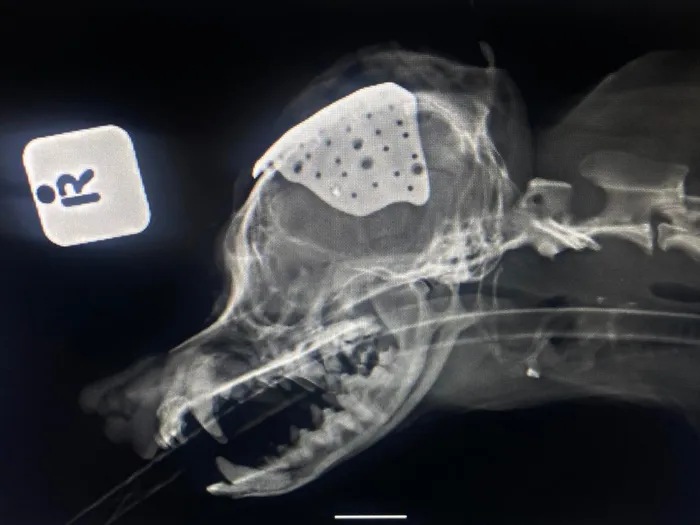

Radiographic side view (right lateral) of Popcorn's skull indicating the irregularly shaped custom  printed titanium plate on top of her skull.

A team of veterinarians from the University of Pretoria’s (UP) – armed  with a “3D-printed skull” – saved the life of Popcorn, an eight-year-old Pomeranian, after she had been bitten by another dog and sustained a severe head injury.

When Popcorn, who was injured during a fight in February, was brought into the Faculty of Veterinary Science’s Onderstepoort Veterinary Academic Hospital (OVAH) in May, her future was uncertain. She had sustained a severe injury known as a comminuted, depressed skull fracture. Comminuted fractures are serious bone breaks, usually caused by high-impact trauma, where the bone shatters into three or more pieces.

Fragments of bone were pressing on and into Popcorn’s brain, leaving her weak, off-balance and at risk of seizures.

“Our team’s first priority was to stabilise her,” says Dr Shannon van Rooyen, surgical resident at the OVAH, who was instrumental in the stabilising process and the surgical procedure. “Once she was strong enough, a CT scan was performed to create a 3D model of her skull. From this, a custom-made titanium plate was designed and printed to fit the outside of her skull perfectly.”

“During the surgery, the loose bone fragments were carefully removed to relieve pressure on her brain, and the titanium plate was placed to reconstruct her skull and protect her from future trauma,” Dr Kitshoff said. After her operation, Popcorn recovered in the hospital’s intensive care unit for two weeks, supported round the clock by the OVAH’s dedicated clinicians and veterinary students, who cared for her with patience and love.